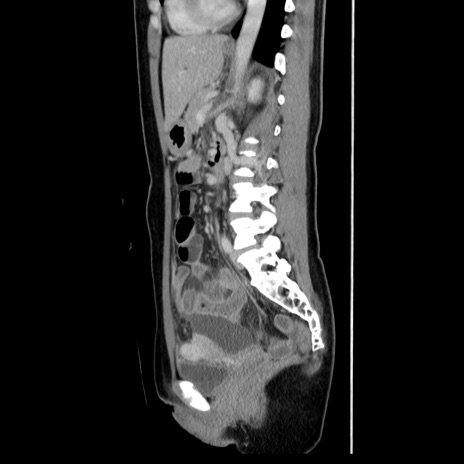

症例39(矢状断像)

【症例】40歳代女性

【主訴】上下腹部痛

【現病歴】2日目から下腹部痛あり。夜間は痛みで眠れなかった。昨日より上腹部痛と下痢が出現。臥位で痛みは軽快したため、休んでいた。本日になって臥位でも立位でも痛みが強くなってきたため救急要請。

【既往歴】子宮内膜症

【身体所見】部:平坦・軟、左上下腹部に圧痛あり、反跳痛あり。

【データ】WBC 21800、CRP 26.78

CT